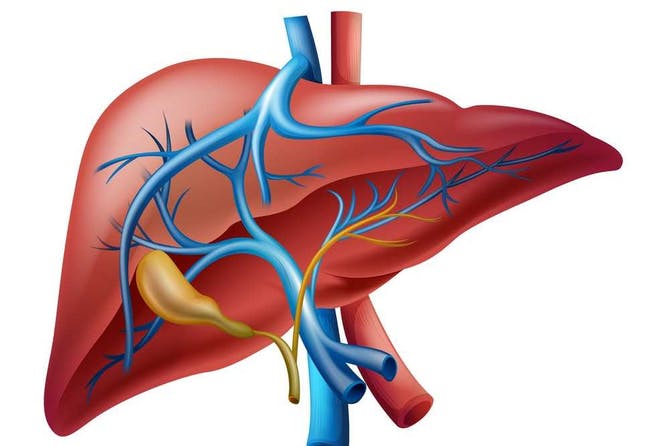

متابعات: يعتبر الكبد من أهم أعضاء الجهاز الهضمي، فهو يحمي الجسم من السموم والمواد الضارة، ويقوم هذا العضو بتحويل العناصر الغذائية إلى طاقة، وتصفية العناصر غير الضرورية. يصبح الكبد ضعيفًا للغاية بسبب نظام الحياة الحديثة، حيث لا يلتزم الشخص غالبًا بالتغذية السليمة ولديه عادات سيئة.

إليك مجموعة من الأطعمة التي تساعد على تجدد أنسجة الكبد وتطهيره من السموم، فيما يلي: